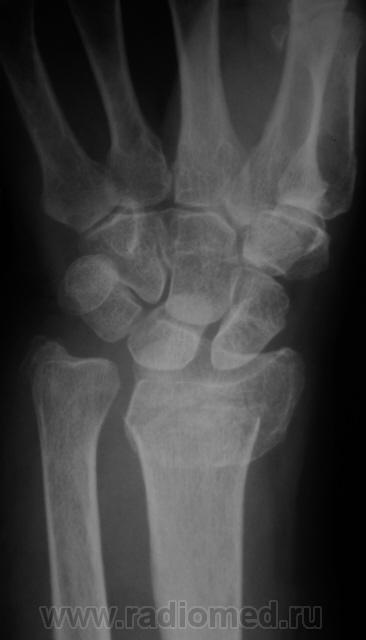

Случай 2.  Пациент направлен врачом хирургом на рентгенографию лучезапястного сустава.

А вот по-поводу второго случая: перелом луча в "типичном" месте, только вот смущает ладьевидная кость - какая-то она патологическая, имеется участок разряжения костной ткани в проекции головки кости или я ошибаюсь?